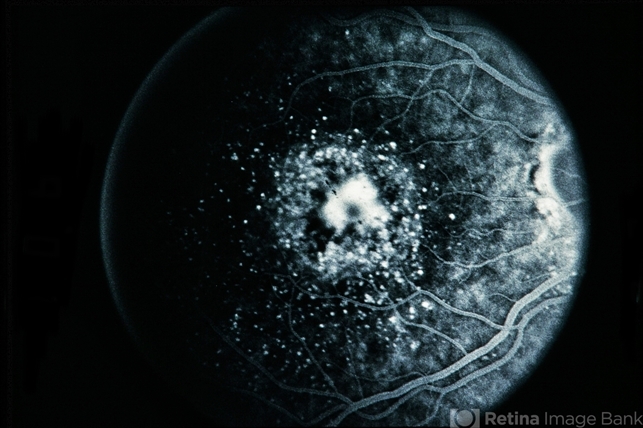

Pseudo Best's / Cuticular Drusen

Pseudo Bests Cuticular Drusen

Best disease, cuticular drusen

47-year-old white female, pseudo Best's / cuticular drusen .